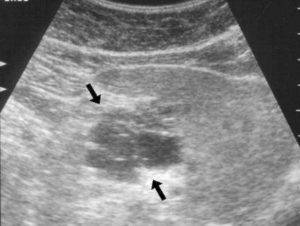

Эхографически и эхоскопически диффузные изменения поджелудочной железы, что может означать данный диагноз?

Эхоструктура поджелудочной железы – это возможность отображать звук при ультразвуковом исследовании. И если в органе есть какие-то изменения, то нарушается и его эхоструктура. Таким образом, Эхографические и эхоскопические диффузные изменения могут свидетельствовать об остром панкреатите, если при этом размеры органа немного увеличены. Это происходит из-за его отечности.

Снижение эхогенности органа при обследовании при его нормальных размерах может означать наличие хронического панкреатита.

Кроме снижения данных показателей они могут и повышаться, это свидетельствует о развитии иных заболеваний. К примеру, повышенная эхогенность при нормальных размерах органа может означать то, что пациент болен липоматозом. Если же орган при этом уменьшается, либо же увеличивается его плотность, то это может быть признаком фиброза поджелудочной железы.